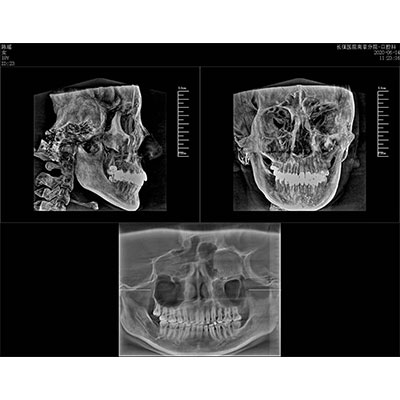

該款牙科CBCT產(chǎn)品采用動態(tài)平板探測器,獲得三維圖像的同時還具有數(shù)字化全景功能,廣泛應用于口腔頜面外科、正畸科、正頜外科、種植科、牙體科、顳下頜關節(jié)科等術前術后。

可同時觀察軸向面、冠狀面和矢狀面圖像,方便臨床診斷。